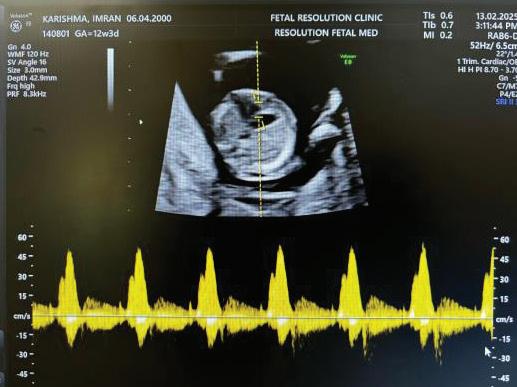

ADDITIONAL SONOGRAPHIC MARKERS:

A Wave Reversal

MARKER

Ductus Venosus flow

Tricuspid Regurgitation

Tricuspid Regurtitation

SIGNIFICANCE

Reversed a-wave in aneuploidy or cardiac dysfunction

Suggests cardiac abnormality or aneuploidy

➢ In fetal cardiology, a large retrospective screening of 77,396 fetuses at 11–13+6 weeks demonstrated a detection rate of ~70.5 % for congenital heart disease (CHD) using a standardised firsttrimester cardiac scanning strategy.2